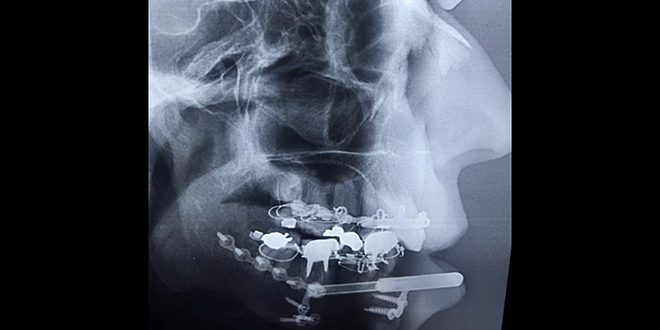

أعاد اختصاصي جراحة الوجه والفم والفكين الدكتور خالد عوف بناء جسم الفك السفلي كاملاً لسيدة خمسينية فقدته جراء أذية شديدة عبر تقنية وجهاز ابتكره سابقا وسجل براءة اختراع فيه.

الدكتور عوف رئيس شعبة جراحة الفكين في مشفى الشرطة أوضح لسانا أن التقنية تطبق للمرة الأولى لبناء عظم الفك السفلي كاملا دون الحاجة لطعوم غيرية أو ذاتية حيث طبقها سابقا بشكل جزئي مبيناً أن السيدة تعرضت لإصابة شديدة وكانت التقنية مثالية لحالتها وأثبتت نجاحها في بناء الفك السفلي بين 20 إلى 25 يوماً.

وذكر عوف أن الجهاز سمح ببناء عظم الفك السفلي وانسجته الرخوة ذاتيا بشكل كامل دون الحاجة لتطعيمه بالغشاء المخاطي أو طعوم عظمية من مناطق بعيدة كالصدر والقدم وغيره مشيرا إلى أن إزالته تتم بعد تكلس العظام وتمعدنه وتشبه فكرة البناء الذاتي للعظم في الجهاز الجديد تقنية تدبير الكسور وهي وضع سطحين عظميين متلاصقين فتتطور الخلايا المصورة بالدم ضمن منطقة الملامسة بينهما لخلايا بانية للعظم تساعد على بناء الفقد العظمي.

وحسب الاختصاصي يغني الجهاز الجديد عن التقنيات المطبقة حالياً والتي تعتمد على أخذ طعوم عظمية من مناطق بعيدة لترميم الفك السفلي وتحتاج إلى ستة أشهر ويضطر الأطباء لوضع عدد كبير من الصفائح وتكون مكلفة ونسبة نجاحها أقل مقارنة بالطريقة الجديدة التي تضمن نسب شفاء عالية وبوقت قصير باعتبار أن العظم يبنى ذاتياً.